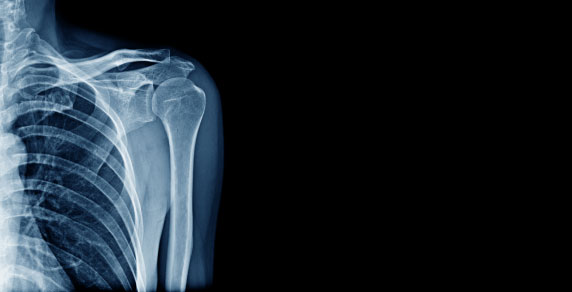

Established since 1999, X-Ray Newstead has been providing high quality, personalised radiology services in Launceston.

With a full accreditation with Quality, Innovation, Performance (QIP) X-Ray Newstead is fully equipped for all general practice, dental x-rays (including Cone beam CT) and ultrasound services.

Launceston is home to the first x-ray photographs in the southern hemisphere, with Frank Styant Browne, creating the first x-ray photograph in 1896. Since then, Launceston has been a pioneer of the latest in x-ray technology.